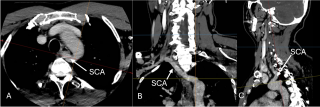

Case presentation

A 57-years-old female was referred to general surgeons for port implantation before starting chemotherapy. Catheter insertion was planned on the right cephalic vein, but its progression proved impossible during the procedure. A right subclavian vein puncture was subsequently performed, allowing the guidewire to cross the right brachiocephalic vein and descend to left side of the heart. While suspecting incorrect placement, the right internal jugular vein was punctured under ultrasound control, yet the guidewire advanced laterally toward the left heart. Upon vascular consultation, images review of previously conducted scan revealed a patent PLSVC, which transversed posteriorly to the left atrium and drained into the right atrium through the coronary sinus. The right SVC was absent, replaced by a left brachiocephalic vein bridge that drained into the PLSVC (Figure 1). The catheter was placed into the PLSVC and the procedure completed (Figure 2). The patient developed a pneumothorax due to subclavian puncture, which was effectively managed by drainage placement, leading to an uneventful recovery.